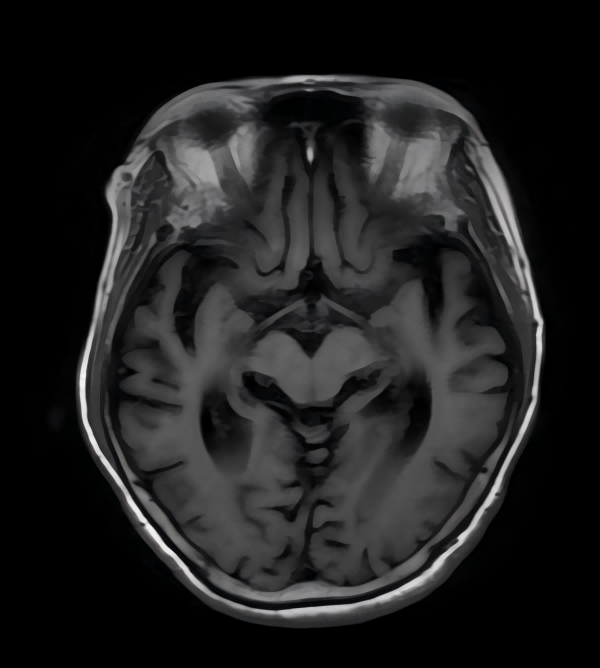

MRI具有无创、无辐射、空间分辨率高的独特优势,是评估阿尔茨海默病的最佳影像检查方法之一。它可以达到毫米级和亚毫米级的分辨率,精细地描绘大脑中神经结构的变化。

阿尔茨海默病最早影响的脑区之一是海马,这是参与学习和记忆的重要脑区。飞鱼影像的核磁检查能够智能化测量海马体积,观察内侧颞叶萎缩情况,发现早期、轻微的大脑变化。

MRI可以帮助医生排除其他疾病造成的痴呆,如脑肿瘤、脑积水等。

飞鱼影像采用多模块先进的MRI技术为阿尔茨海默病评估提供全面信息:结构磁共振(sMRI)可测量大脑皮层的体积和厚度来反映结构变化;弥散张量成像(DTI)能有效观察和追踪脑白质纤维束,直接从微观水平反映神经元功能的改变;静息态功能磁共振(r-fMRI)可以探测到局部脑区神经元活动情况。